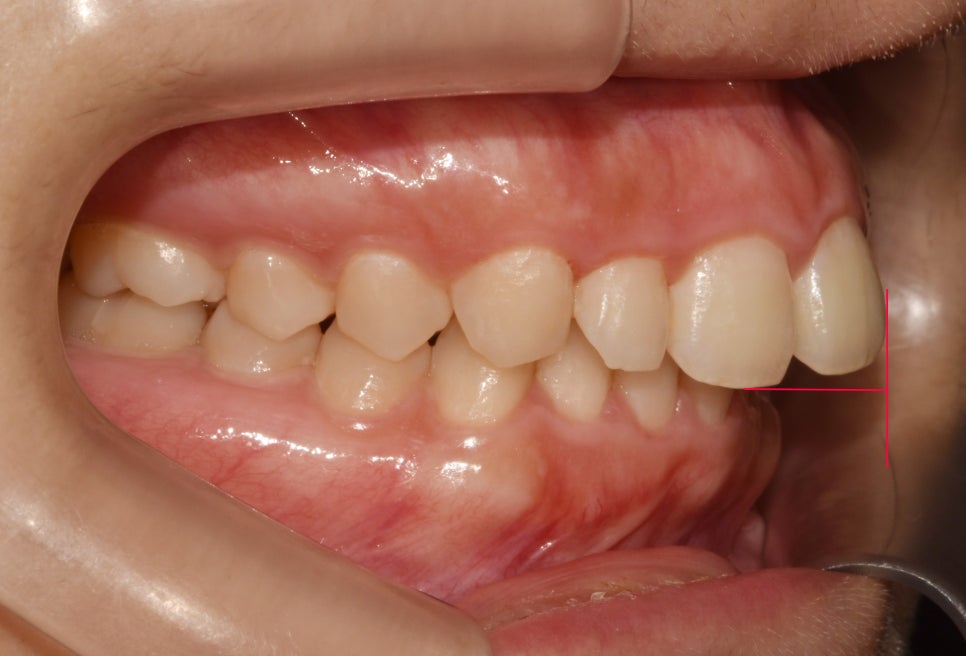

“그러나 딥바이트 (deep bite)를

가졌을 경우에는 아래쪽 앞니를

4mm 이상 깊게 덮으며,”

심한 경우에는 위에 있는 사진처럼

아랫니가 거의 보이지 않을 정도로

깊게 겹쳐 보여질 수 있습니다.

앞서 설명드린 딥바이트의 형태를

가지고 있어 깊게 물리는 느낌이 듭니다.

윗니에 비해 이미 아랫니는

80% 정도가 깊게 가려져 있어

과개교합 교정이 필요하네요.